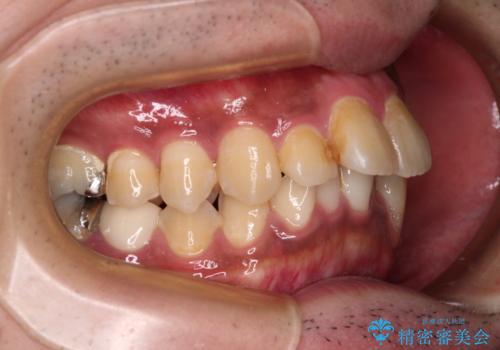

- 主張してる上の前歯を気にして来院された患者様です。

上の前歯が出ているものの、口元が出っ歯というわけではなかったため、非抜歯矯正にて治療を行うこととしました。

下顎に対して上顎歯列が全体的に前方に位置しており、特に右側の奥歯の咬み合わせの前後のズレが大きいため、補助装置を用いて咬み合わせを改善することとしました。

元々むし歯リスクが高かった上に、矯正治療中も磨き残しが多かったため、今後はむし歯治療を行う必要があります。